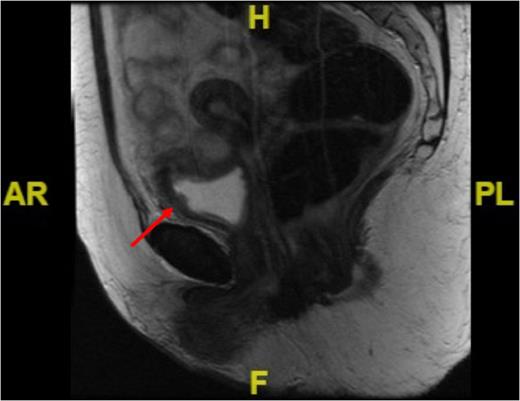

A 62-year-old female presented with a 5-day history of visible haematuria. Clinical examination was unremarkable. Full blood count analysis revealed a haemoglobin of 58 g/L prompting transfusion of 3 units of packed red cells. An ultrasound scan (USS) identified an abnormal soft tissue mass arising from the superior aspect of the urinary bladder with vascular flow within it, raising the suspicion of a malignant neoplasm (Fig. 1).

Initial admission USS of the urinary bladder demonstrating a solid mass within it (see red arrow).